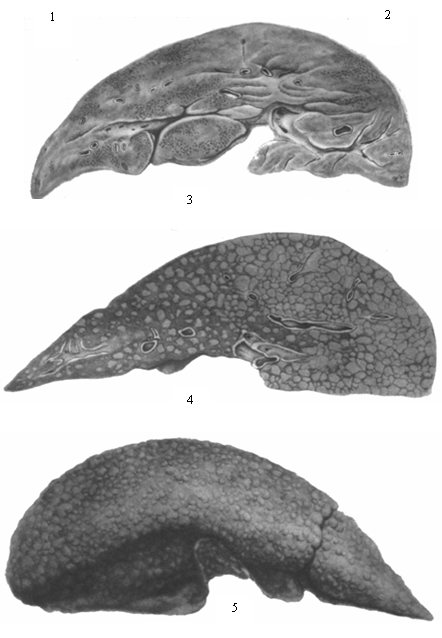

2.

Хронический прогрессирующий гепатит с рецидивами и обострениями

характеризуется сочетанным диффузным поражением паренхимы и стромы печени и

соответствует клинико-анатомическому понятию цирроза печени (см. рис. 4 и отд.

табл., рис. 4 и 5). Имеющиеся при этом воспалительные инфильтраты в строме,

дистрофически некротические изменения печеночного эпителия, процессы узловой

регенерации, диффузное разрастание соединительной ткани с нарушением сосудистой

структуры, с образованием портально-печеночных анастомозов ведут к полной

перестройке печени, вовлекая в страдание ряд органов и систем организма. В

В

небольшом проценте случаев обычное течение Б. б. осложняется массивным некрозом

печеночных клеток, что сопровождается клинической картиной острой недостаточности

печени и квалифицируется анатомически как острая токсическая дистрофия печени

или острая атрофия. Отмечаемые макроскопически дряблость печени и уменьшение ее

размеров (рис. см. отд. табл., рис. 3) зависят но только от гибели паренхимы,

но и от уменьшения кровенаполнения в спавшейся строме. При более медленном

развитии некрозов — при подострой дистрофии печени — на фоне большой убыли

паренхимы и воспалительных инфильтратов четко выступают процессы регенерации и

некоторая коллагенизация стромы, что обусловливает более плотную консистенцию

печени. Исход острой и подострой дистрофии печени — летальный или в узловую

гиперплазию с рубцеванием, или в постнекротический цирроз печени.

печеночных клеток. Рис. 3. Болезнь Боткина, осложнившаяся острой

токсической дистрофией печени (девочка 1 года). Дряблая, уменьшенная,

спавшаяся печень (на разрезе). Рис. 4 и 5. Лаеннековский цирроз печени в

исходе болезни Боткина (девочка 12 лет, длительность заболевания 5 лет). Диффузные

узлы регенератов, окруженные фиброзной тканью (рис. 4—на разрезе, рис. 5— с

наружной поверхности печени).